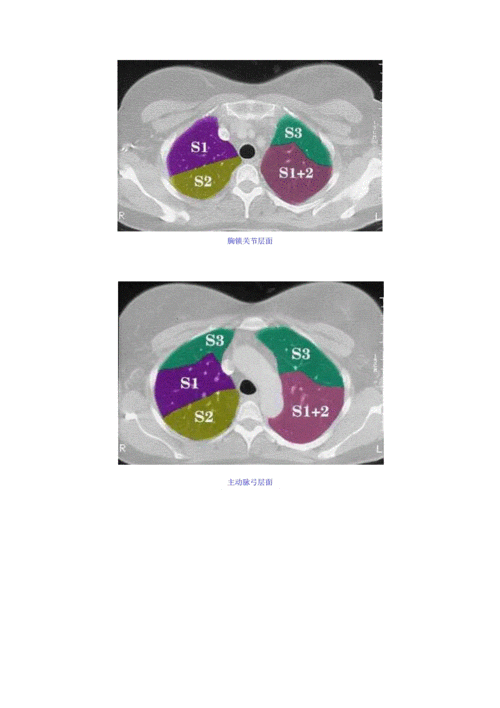

肺野如何划分

肺野如何划分,肺野的划分

肺野的划分

胸部ct肺段划分口诀doc

如何在ct上区分肺叶和肺段说课材料.ppt 17页

肺段的划分ppt

正常肺段的划分.doc

肺野的划分图

胸片肺野的划分

肺野分区

肺野分区图

肺段划分